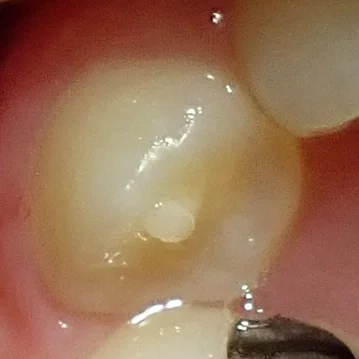

・中心結節

これは前から4番目・5番目の歯(小臼歯)に多く起こってくる形態異常の1つです。

こういうやつですね。

これの何が不味いかって、この突起の中に神経が入っていることがあるんですよね。

そして、ここはかみ合わせなどですり減ったり、折れたりすることで、神経が口の中に露出してしまう事があります。